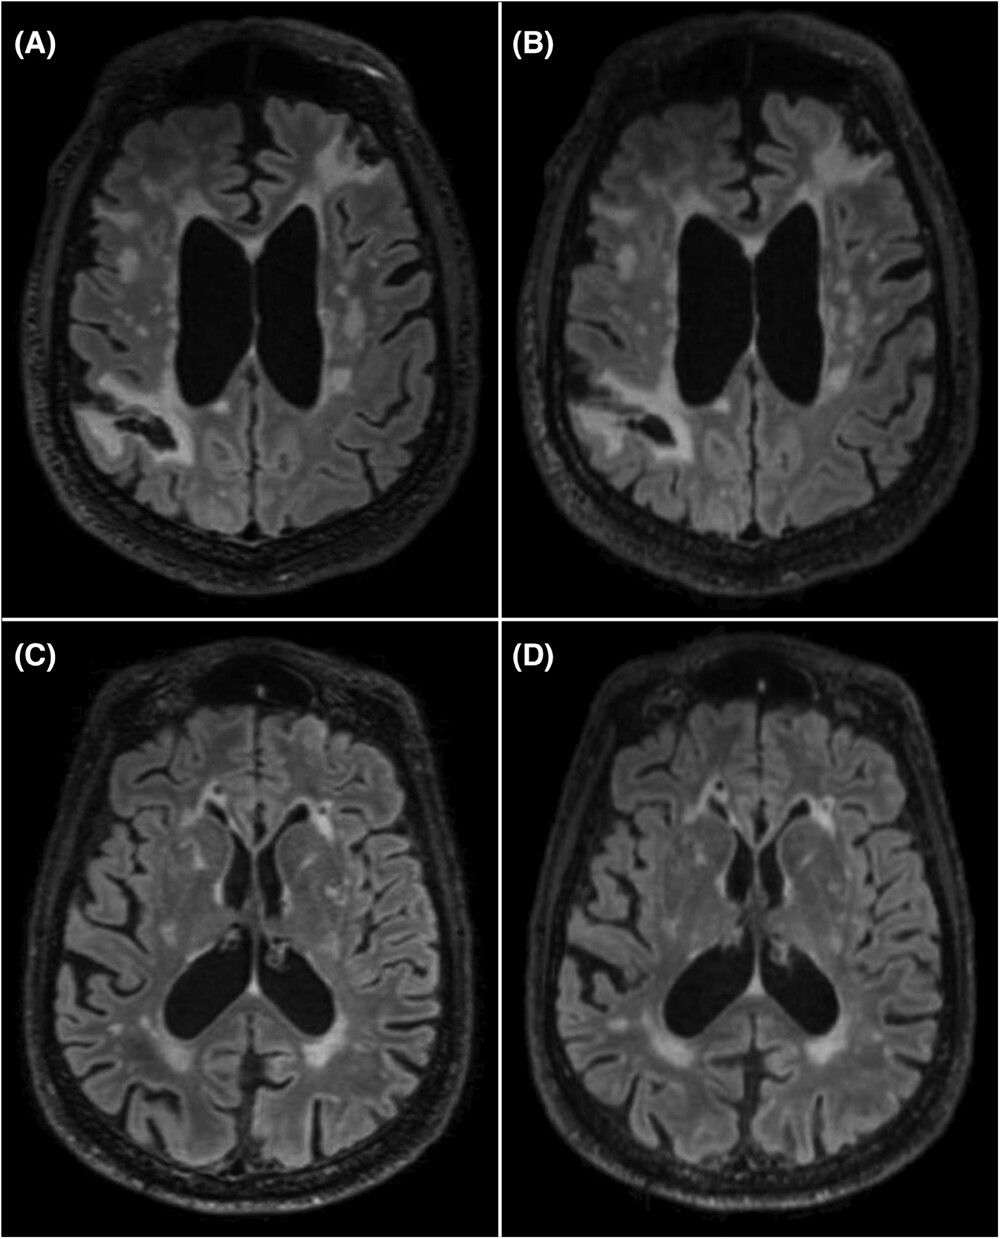

Examples of MRI sequences from the clinical (A, C) and fast (B, D) protocols. Figure from Rosa-Grilo M et al. (2025). doi: 10.1002/alz.70341

Overall, total acquisition (scan) time was markedly reduced, by 63%, so the scan could be performed in one third of the time taken previously. Reliability of the neurologist’s assessments of the newly accelerated protocol was not inferior to the standard of care protocol.